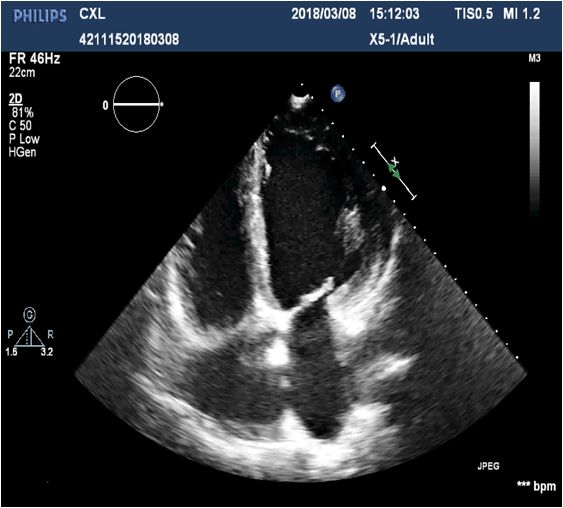

重症超声

1、下腔静脉变异度9 %

2、右心无增大

3、左室收缩功能降低

(EF=46% EDV=106ml SV=48ml)

左室舒张功能降低

4、肺部超声肺间质综合征